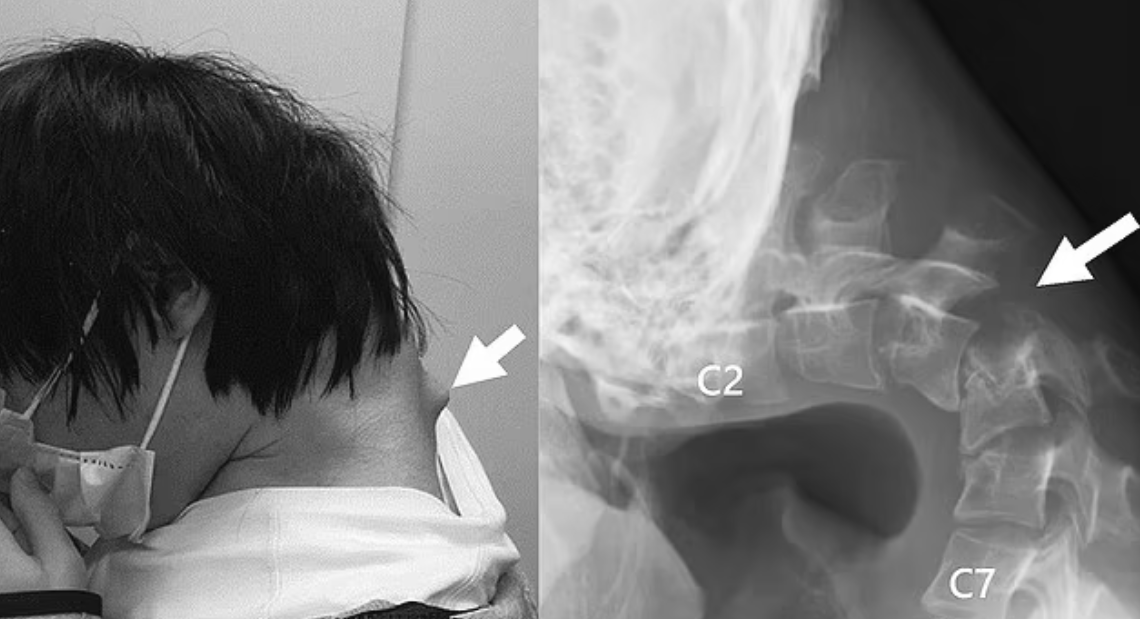

Fotografiile tulburătoare arată o umflătură proeminentă pe gâtul său, cauzată de deformarea vertebrelor din cauza poziției nenaturale, potrivit Daily Mail.

Investigațiile realizate de medici au arătat că vertebrele gâtului pacientului deveniseră deformate și dislocate, iar în coloană s-a dezvoltat țesut asemănător cicatricilor, ca urmare a poziției incorecte menținute în timp.